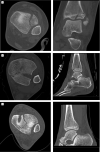

Aims: Understanding the orientation of fracture lines and mechanisms is the essential key to sufficient surgical therapy, but there is still a lack of visualization and teaching methods in traumatology and fracture theory. 3D-printed models offer easy approach to those fractures. This paper explains the use of the teaching possibility with 3-dimensional models of transitional fractures of the ankle.

Methods and results: For generating 3D printable models, already obtained CT data were used and segmented into its different tissues, especially parts concerning the fracture. After the segmentation process, the models were produced with FFF (fused filament fabrication) printing technology. The fracture models then were used for hands-on teaching courses in AO course (Arbeitsgemeinschaft für Osteosynthesefragen) of pediatric traumatology in 2020 in Frankfurt. In the course fracture anatomy with typical fracture lines, approaches, and screw placement could be shown, discussed and practiced.

Conclusion: The study shows the use of 3D-printed teaching models and helps to understand complicated fractures, in this case, transitional fractures of the ankle. The teaching method can be adapted to numerous other use cases.